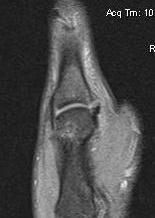

MRI

Anatomy

A. Undisplaced

Distal tear of ulna collateral ligament on coronal MRI

B. Displaced UCL

Coronal MRI demonstrating displaced distal UCL avulsion